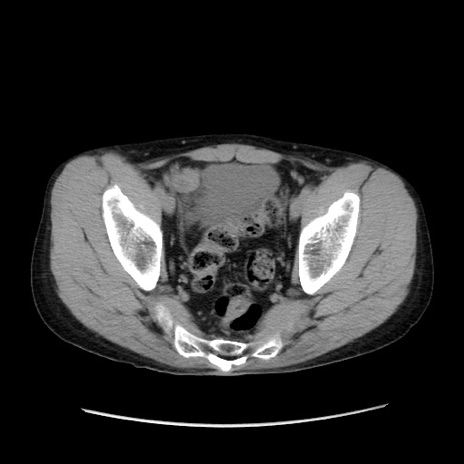

症例37(横断像)

【症例】40歳代 男性

【主訴】腹痛

【現病歴】4時間ほど前に電車に乗車中に臍部上より腹痛出現。徐々に増悪し起立困難となり、救急外来受診。生ものは数日食べていない。今朝お雑煮を食べた。

【身体所見】BT 36.8℃、BP 117/84mmHg、HR 91/min、SpO2 97%、苦悶様、腹部:臍上部広範囲圧痛あり、反跳痛±

【データ】WBC 8100、CRP 0.03